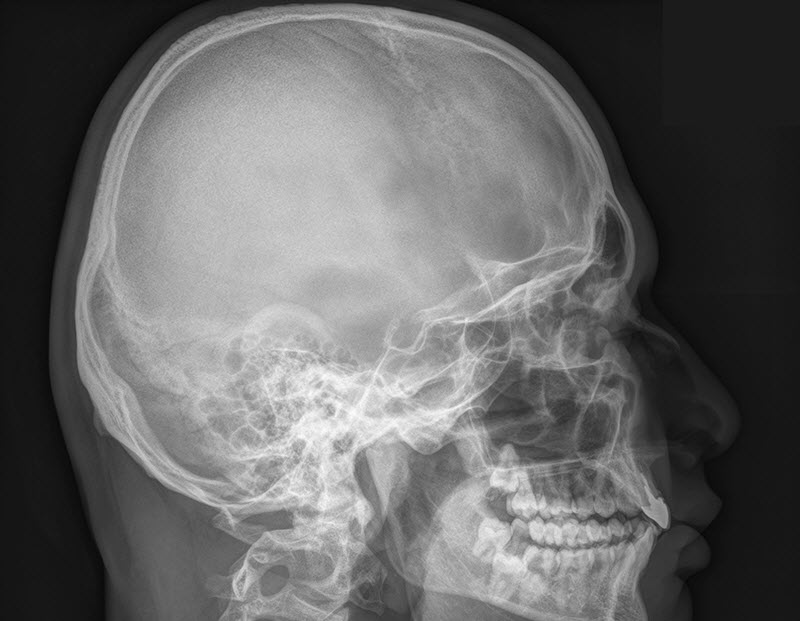

Сложности диагностики

Неврологическое обследование при наличии патологий может давать неоднозначные результаты. Обычное рентгеновское изображение головного мозга не предоставляет достаточной информации. Магнитно-резонансная томография (МРТ) является единственным на данный момент специфическим методом диагностики, который позволяет подтвердить наличие патологии. На основе полученных данных невролог разрабатывает дальнейшую стратегию лечения. Эта стратегия зависит от степени выраженности аномалии, продолжительности клинических симптомов и индивидуальных характеристик пациента. Игнорировать такой диагноз нельзя, так как это может негативно сказаться на прогнозе.